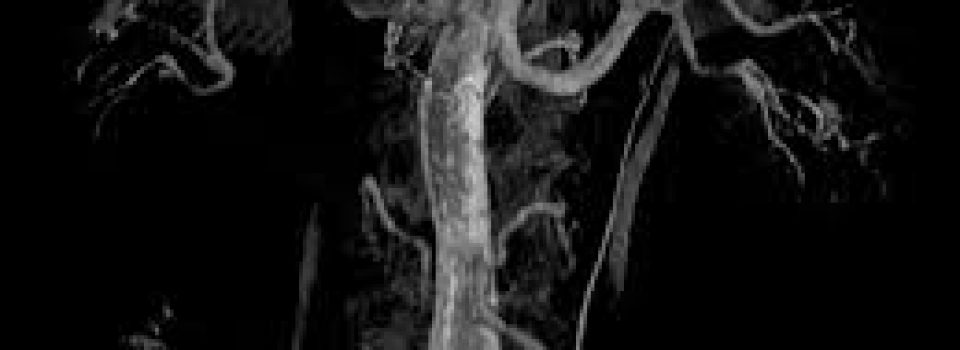

L’angioplastie (dilatation) périphérique ou angioplastie transluminale périphérique  se pratique sous anesthésie locale sur différentes artères au niveau

-des jambes (artères iliaques, fémorales, poplitées … )

-des reins  (artères rénales)

-du cou  (artères carotides )….